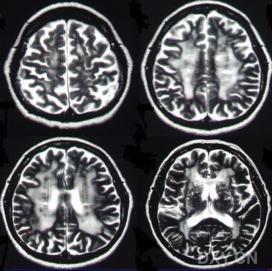

側腦室其發生機制不詳,可能與酒精對腦的直接損害及營養障礙,尤其是維生素B1的缺乏有關。多見於長期大量飲酒的男性中老年人。發病隱匿,緩慢進展。早期常有焦慮不安、頭痛、失眠、乏力等。逐漸出現智力衰退和人格改變。此外,部分病人還可合併有周圍神經病變、肌肉萎縮,甚至出現震顫、幻覺、妄想和癲癇發作等嚴重酒精中毒的表現。頭顱CT示側腦室對稱性擴大,腦溝、半球間裂和外側裂增寬等腦萎縮的表現。

大腦神經元 一次CT掃描發現腦溝加深,腦裂變寬、腦室對稱性擴大等腦萎縮的改變,並不代表腦組織不可逆的喪失。近年來通過CT或MRI研究,發現有些酗酒者所見的這種CT改變在不同程度上是可逆的。這種可逆性說明是腦內液體發生了轉移,而非腦組織喪失。這可能與戒酒後腦中水和電解質恢復正常有關。也可能與腦膠質細胞和神經元蛋白的再生有關。

這些影像學的發現與臨床的相關關係遠沒有弄清。有些患者腦萎縮常伴有明顯酒精中毒性併發症,有報導Wernicke-Korsakoff綜合徵的病理資料,約1/4顯示側腦室、第三腦室擴大,以及額葉腦回萎縮。另一些酗酒者則因反覆發作的癲癇史或有肝病、腦外傷以及其他一些因素而導致腦室擴大。然而,有些酗酒者雖發現腦室擴大,但在整個過程中,常規的神經系統查體和智慧型狀態測試,並未發現有神經精神疾病的症狀和體徵。

4、頭顱CT示腦溝增寬、腦回變小、腦池和腦室擴大等腦萎縮的表現。